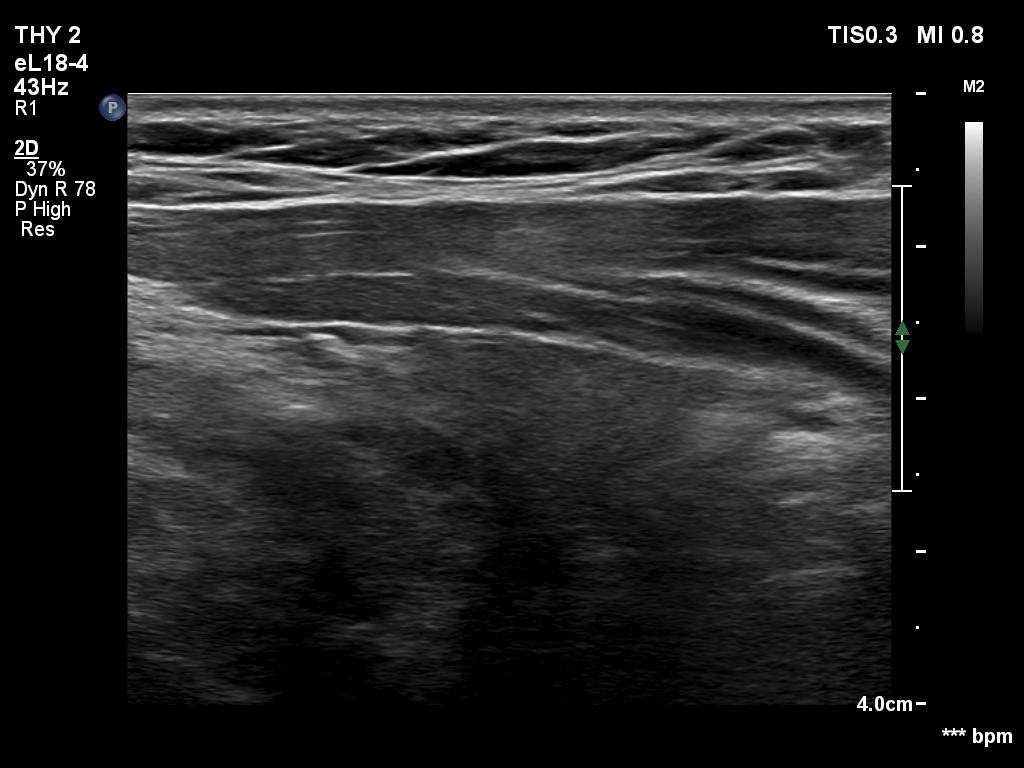

Ultrasonography. The thyroid was hypoechogenic. There was an iso/hyperechoic nodule in both the right and left lobes. The nodule in the left lobe had perinodular vascularity. The dimensions of the nodule in the left lobe were 20x18x31 mm, width, depth, length, respectively. This means that the volume of the nodule has increased almost 8-fold in 10 years.